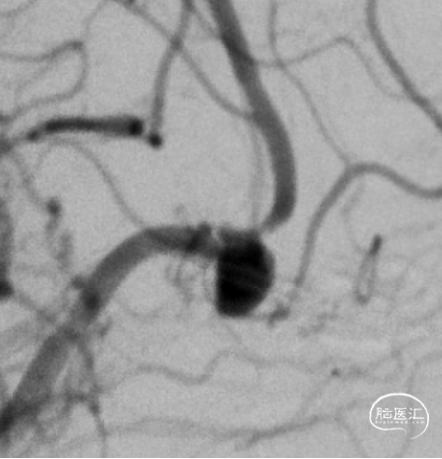

DSA

右侧:平均宽度(5.5+3.9)=4.7mm,最小深度2.8mm,选择SL5x2

VIA微导管到位\WEB释放

WEB释放后造影

术后造影

术后CT